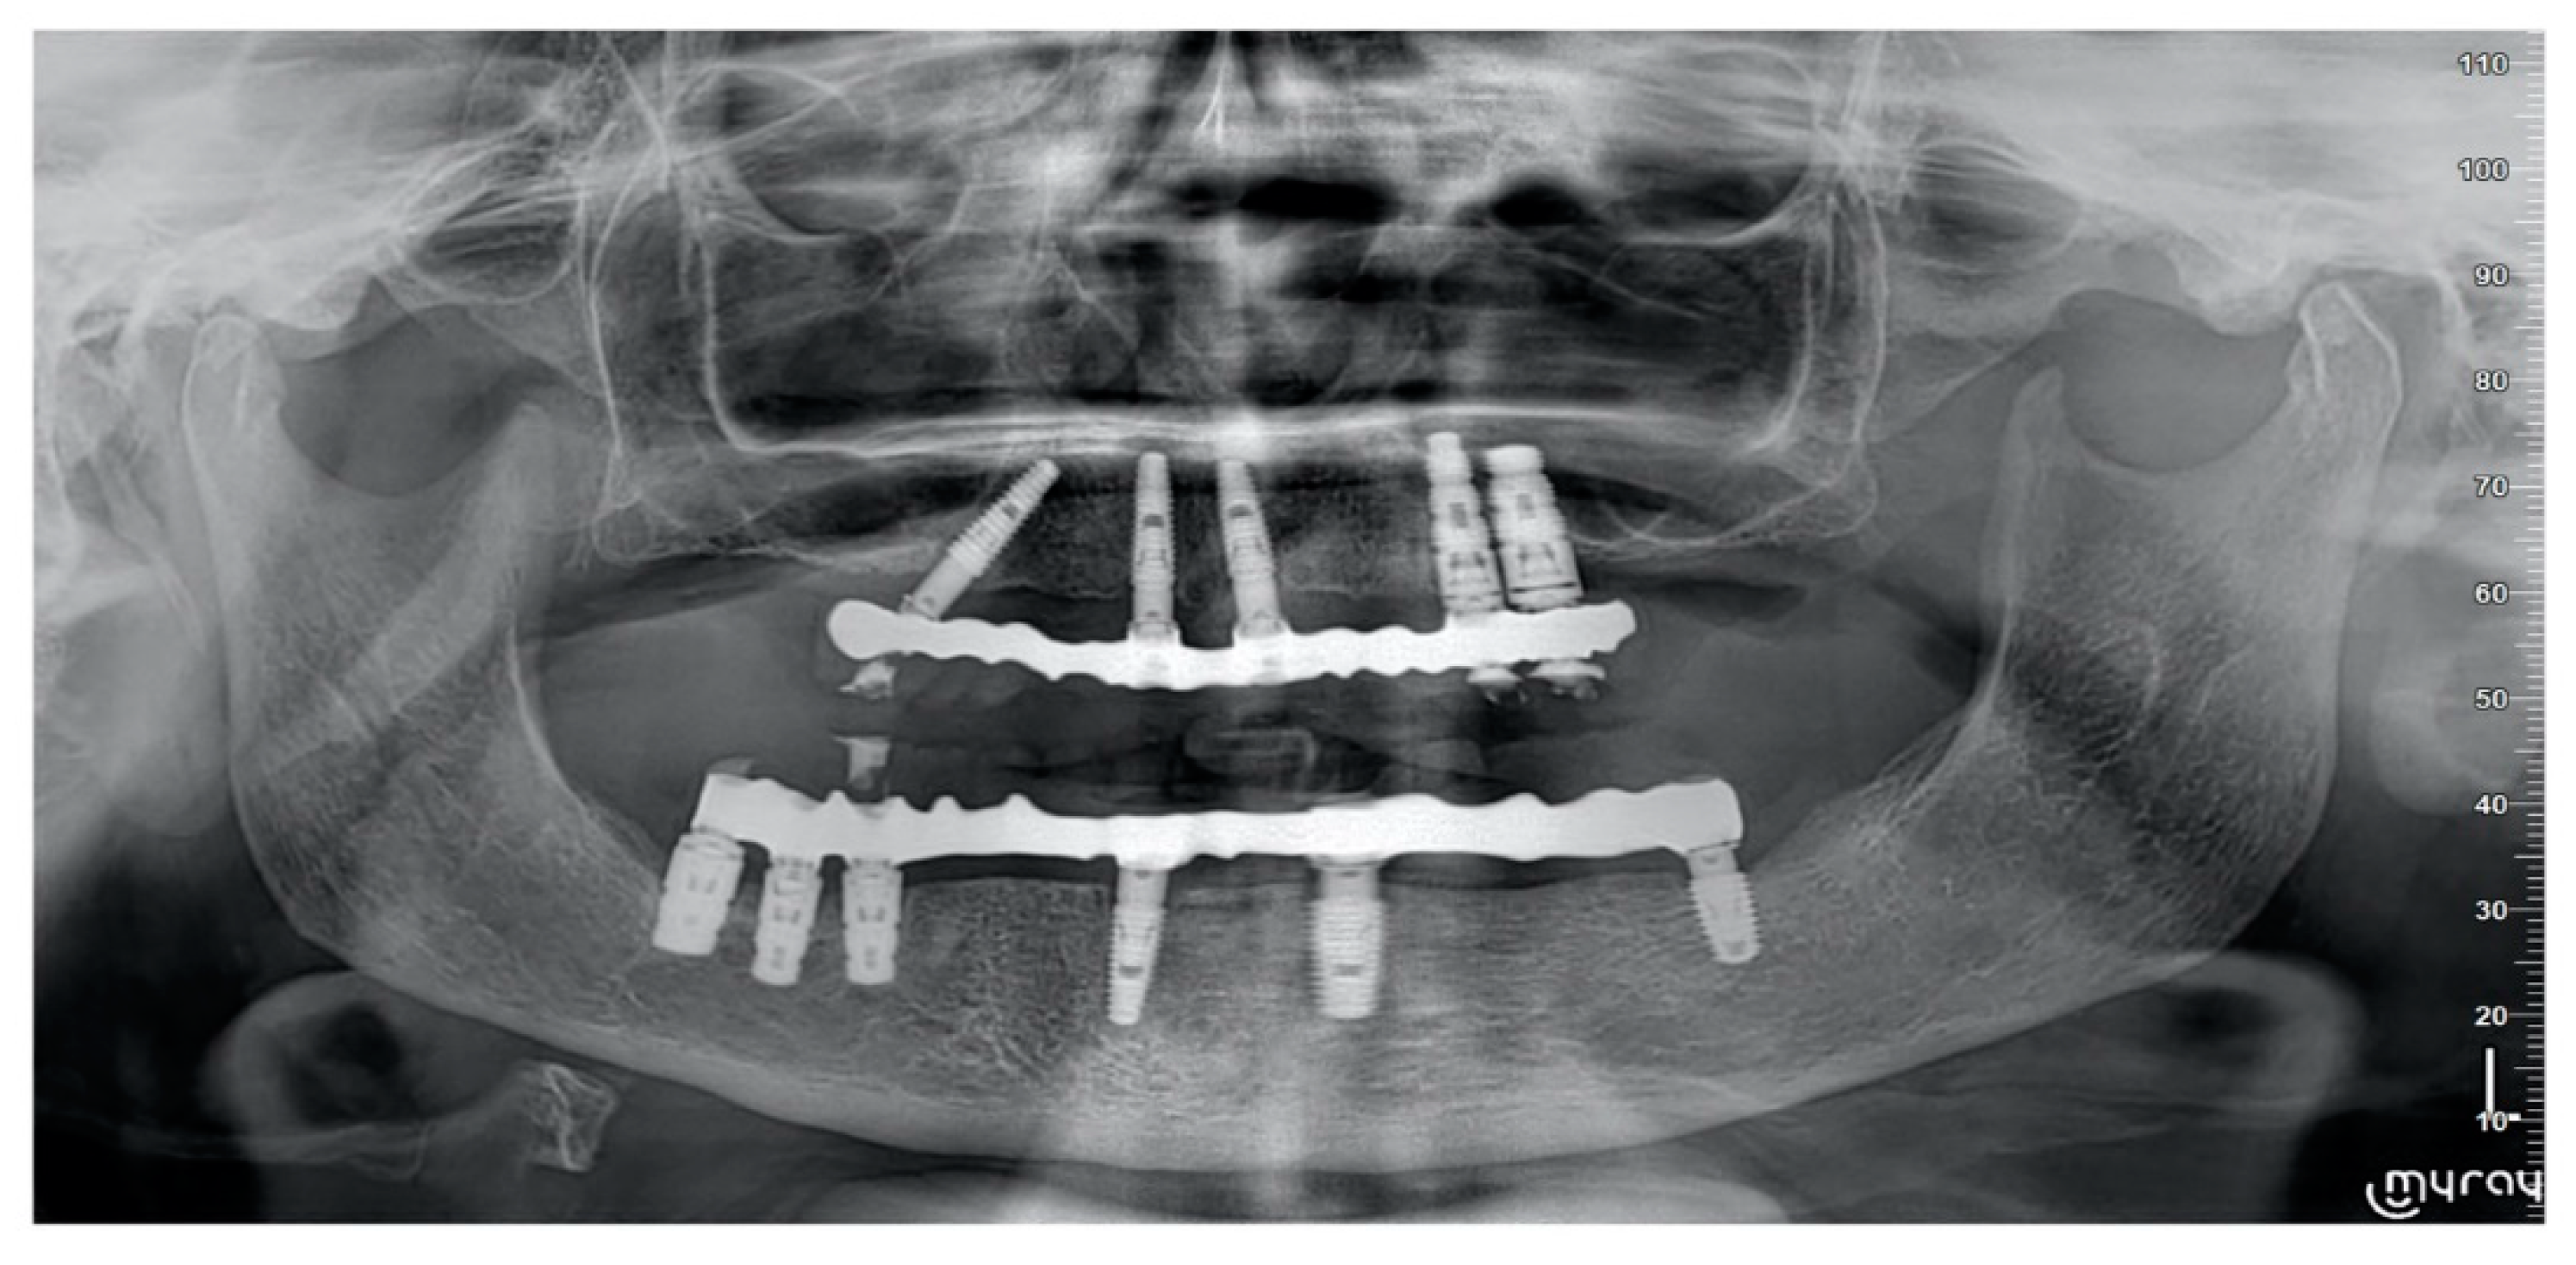

- Marginal bone levels were measured as the distance between the implant platform to the first bone to implant contact. Mean values of mesial and distal measurements were calculated for each implant. Marginal bone level was measured on digital periapical radiographic images obtained by parallel technique with Rinn’s film holder (Rinn XCP, Dentsply, Elgin, IL, USA) taken at definitive implant loading (baseline) and then one year after. All radiographs were analyzed through a dedicate software (DFW2.8 for Windows, Soredex, Tuuka, Finland), calibrated for each image using the known distance between two consecutive threads. The difference between baseline and last follow-up was taken as marginal bone loss. One dentist at each center, not previously involved in this study, performed every radiographic measurement.

4. Results